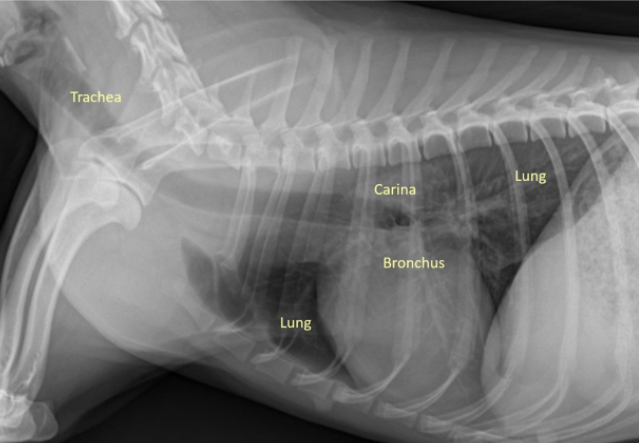

| Airways |

| 정상적인 공기의 흐름 : Trachea - Bronchus - Bronchioles - Lung |